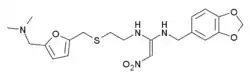

Несмотря на значительные усилия, длительное время не было найдено вещество, тормозящее кислотостимулирующее действие гистамина, и, только в 1972 году Джэймс Блэк, работавший в фирме «Smith Kline and French» (сегодня относится к фирме «GlaxoSmithKline»), Великобритания, испробовав более 700 разных структур, обнаружил, что соединение буримамид, содержащее имидазольное кольцо в боковой цепи, действует на рецепторы желудка (позже названые H2-рецепторами). За идентификацию H2-рецепторов и разработку лекарственных средств, блокирующих их, Блэк в 1988 году был удостоен Нобелевской премии[1].

Принята следующая классификация H2-блокаторов по поколениям[4]:

- I поколение — циметидин,

- II поколение — ранитидин,

- III поколение — фамотидин,

- IV поколение — низатидин,

- V поколение — роксатидин.